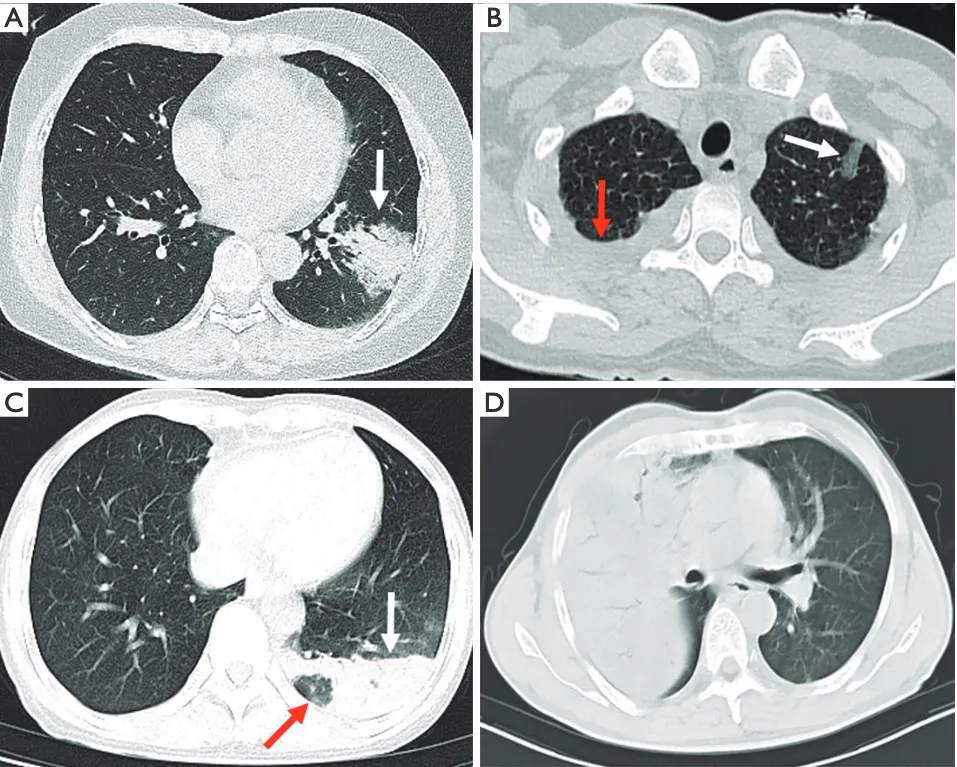

- 进展期:病变进展迅速,实变(98%)伴支气管充气征(80%),可伴细网格征(Fine mesh sign)(74%),实变周围 GGO(晕征)(10%),单侧肺累及多见(62%),可累及双肺(图 4),无坏死、空洞与树芽征,胸腔积液(66%),以单侧居多,部分可伴纵隔淋巴结肿大(36%)[7]。(注:鹦鹉热肺炎病灶累及间质,细网格征对应的就是小叶间隔增厚)

图 4 鹦鹉热患者的胸部 CT。(A)病灶沿支气管血管束分布,与支气管血管束平行(白箭头),可见支气管充气征,中心可见实变,外周有 GGO。(B)病灶表现为次级肺小叶 GGO(白箭头),伴双侧胸腔积液(红箭头)。(C)病灶沿胸膜分布(白色箭头),实变病灶内有部分正常肺实质(pulmonary lobule idling sign,肺叶空置征)(红色箭头),提示病灶内部分次级肺小叶未累及,CT 表现为低密度影。(D)整个肺叶病灶弥漫,伴支气管充气征,支气管受压狭窄但仍未完全阻塞。